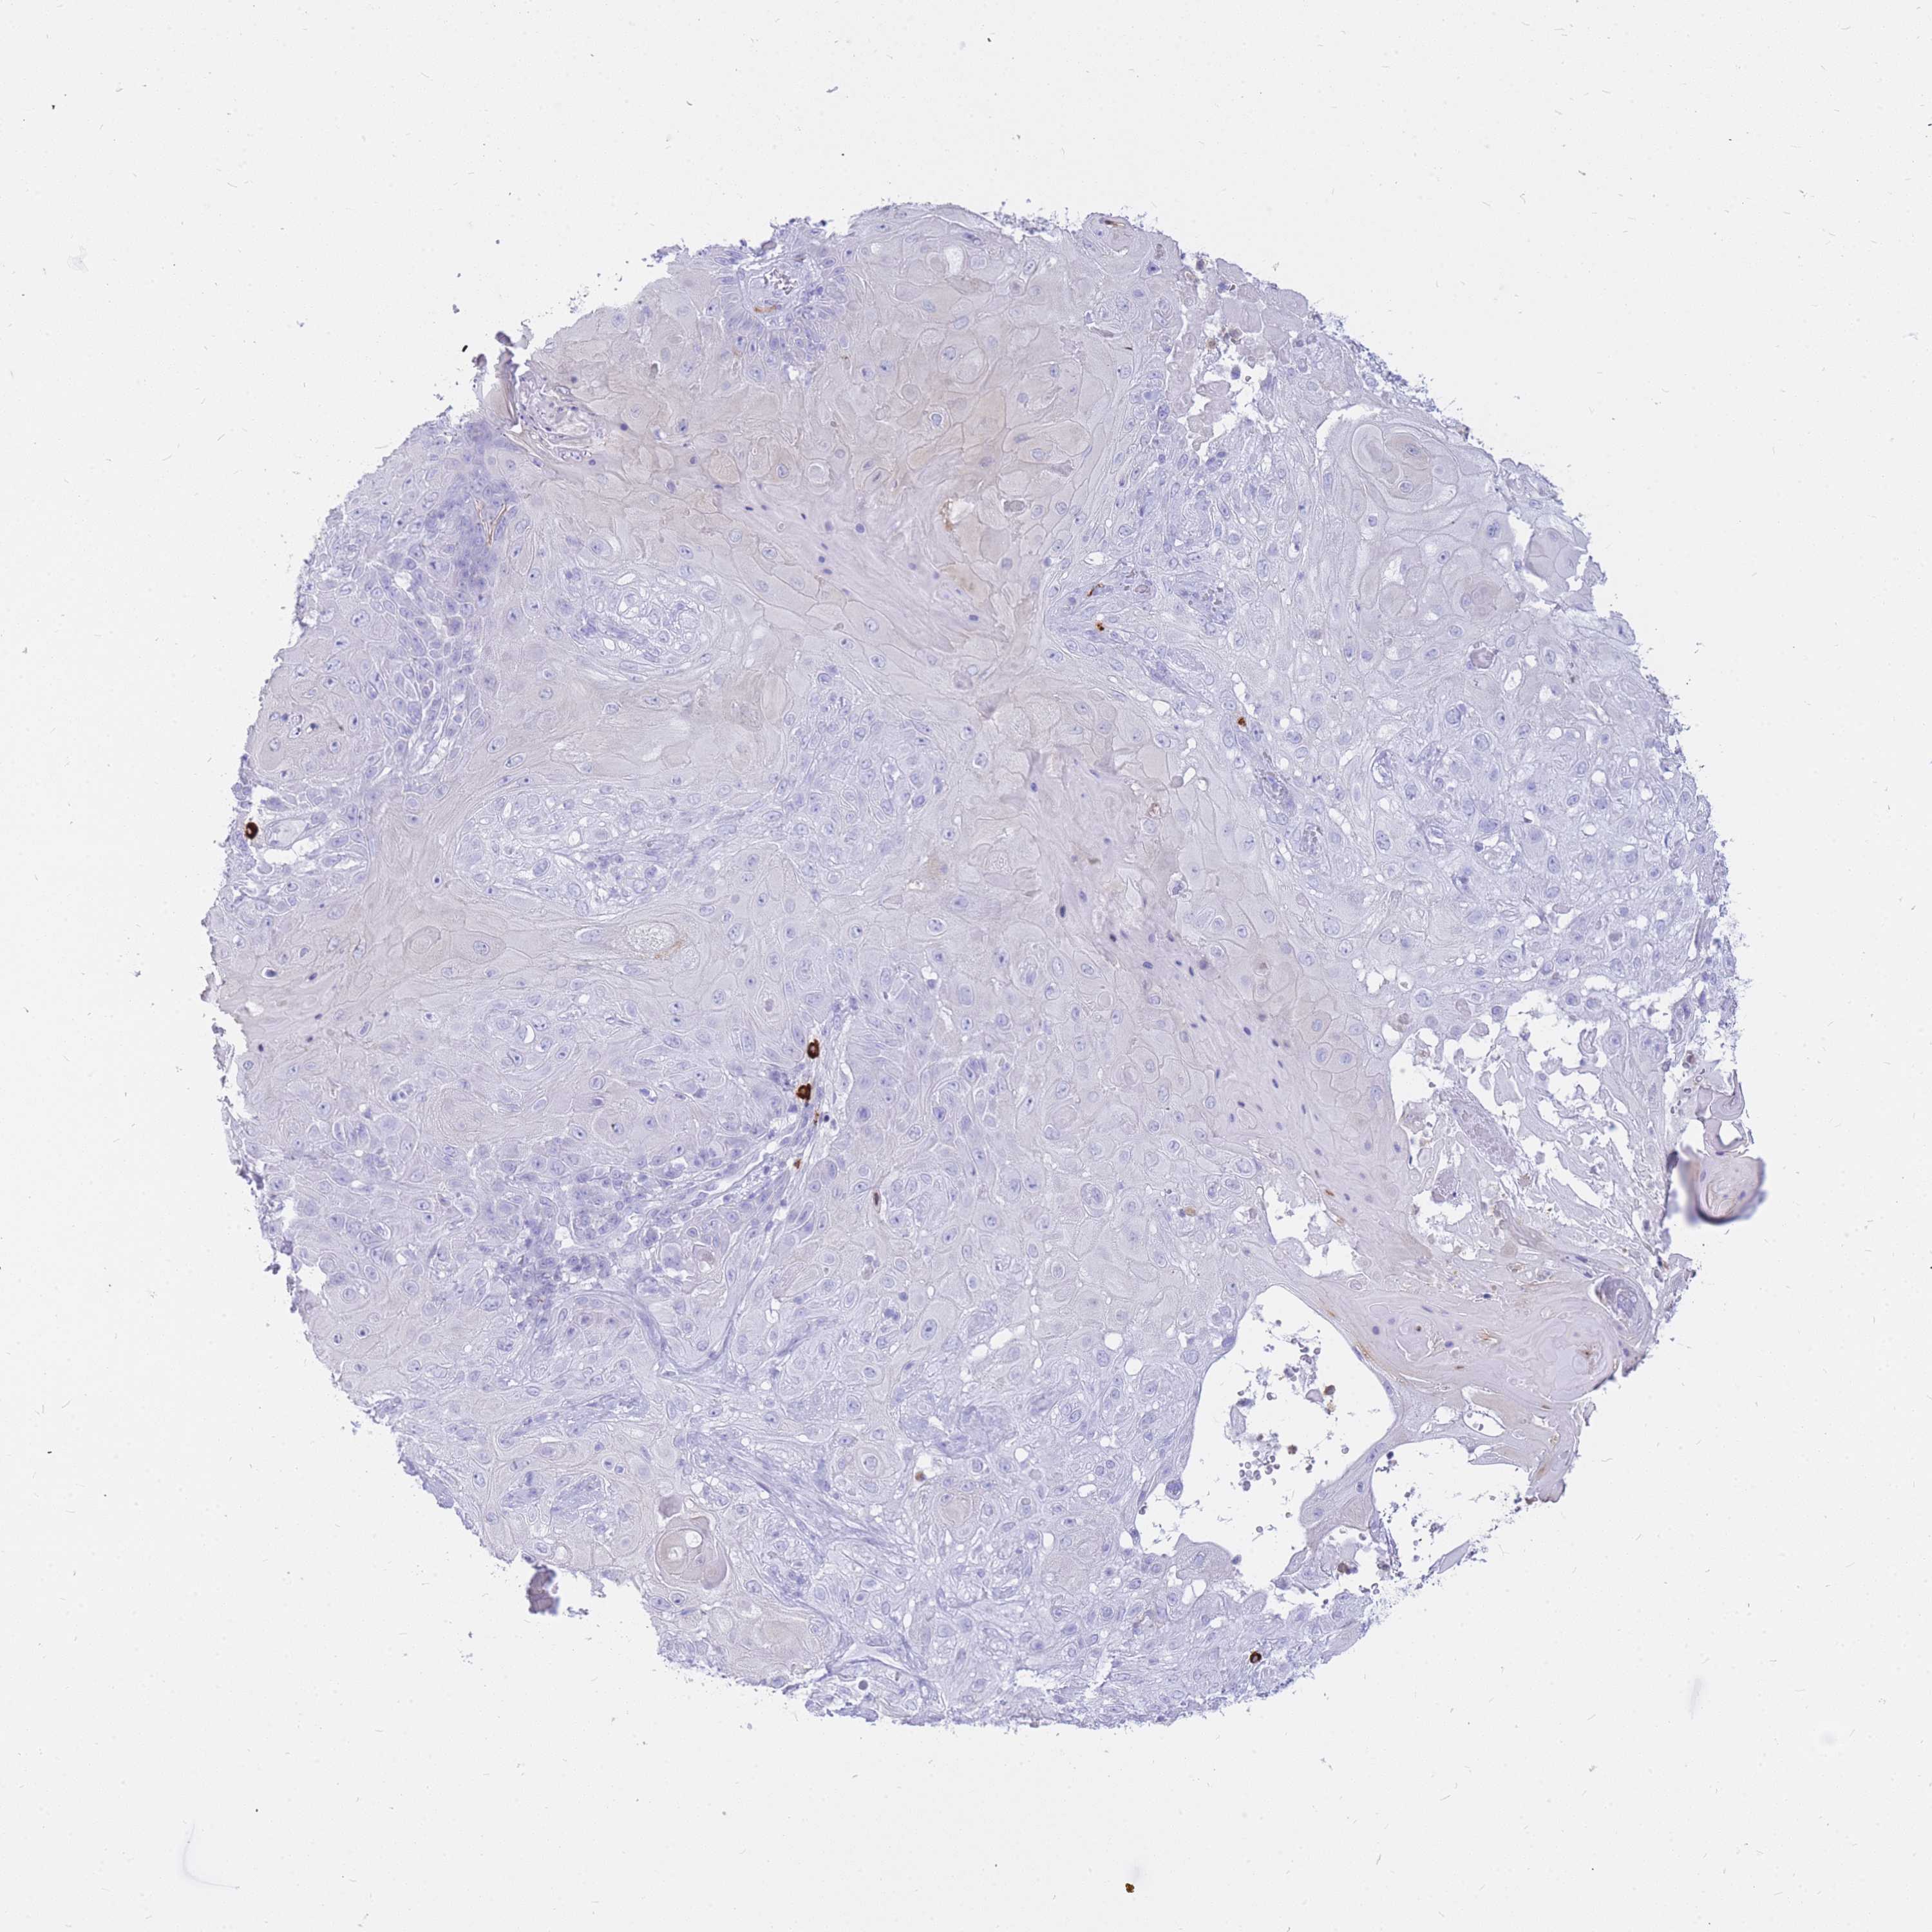

SKIN CANCER - Protein expressioni

A mouse-over function shows sample information and annotation data. Click on an image to view it in a full screen mode. Samples can be filtered based on level of antibody staining by selecting one or several of the following categories: high, medium, low and not detected. The assay and annotation is described here.

Antibody stainingi

Antibody staining in the annotated cell types in the current human tissue is reported as not detected, low, medium, or high, based on conventional immunohistochemistry profiling in selected tissues. This score is based on the combination of the staining intensity and fraction of stained cells.

Each image is clickable and will lead to virtual microscopy that enables deeper exploration of all samples and also displays staining intensity scores, fraction scores and subcellular localization as well as patient and tissue information for each sample.

Antibody HPA049749

Staining

High

Medium

Low

Not detected

Intensity

Strong

Moderate

Weak

Negative

Quantity

>75%

75%-25%

<25%

None

Location

Nuclear

Cytoplasmic/membranous

Cytoplasmic/membranous,nuclear

Squamous cell carcinoma, NOS

Squamous cell carcinoma, metastatic, NOS